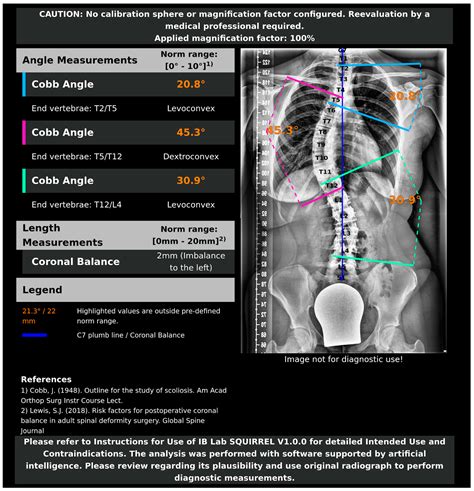

The Cobb Angle Scoliosis is a standard measurement used to quantify the degree of spinal curvature in patients with scoliosis. It is named after Dr. John Robert Cobb, who developed the method in 1948. The angle is measured using an X-ray of the spine, specifically focusing on the most tilted vertebrae at the top and bottom of the curve.

• Obtain an X-ray of the spine, typically a standing posterior-anterior (PA) view.

• Identify the most tilted vertebrae at the top and bottom of the curve.

• Draw a line along the endplate of each of these vertebrae.

• Draw perpendicular lines to these endplate lines.

• Measure the angle formed by the intersection of these perpendicular lines.

This angle is the Cobb Angle Scoliosis, and it provides a quantitative measure of the spinal curvature.

Interpreting the Cobb Angle

The Cobb Angle Scoliosis is used to classify the severity of scoliosis into different categories:

Cobb Angle Range Severity Classification

0-10 degrees Minimal or no curve

11-25 degrees Mild scoliosis

26-40 degrees Moderate scoliosis

41 degrees and above Severe scoliosis

These classifications help healthcare providers determine the best course of action for managing the condition.